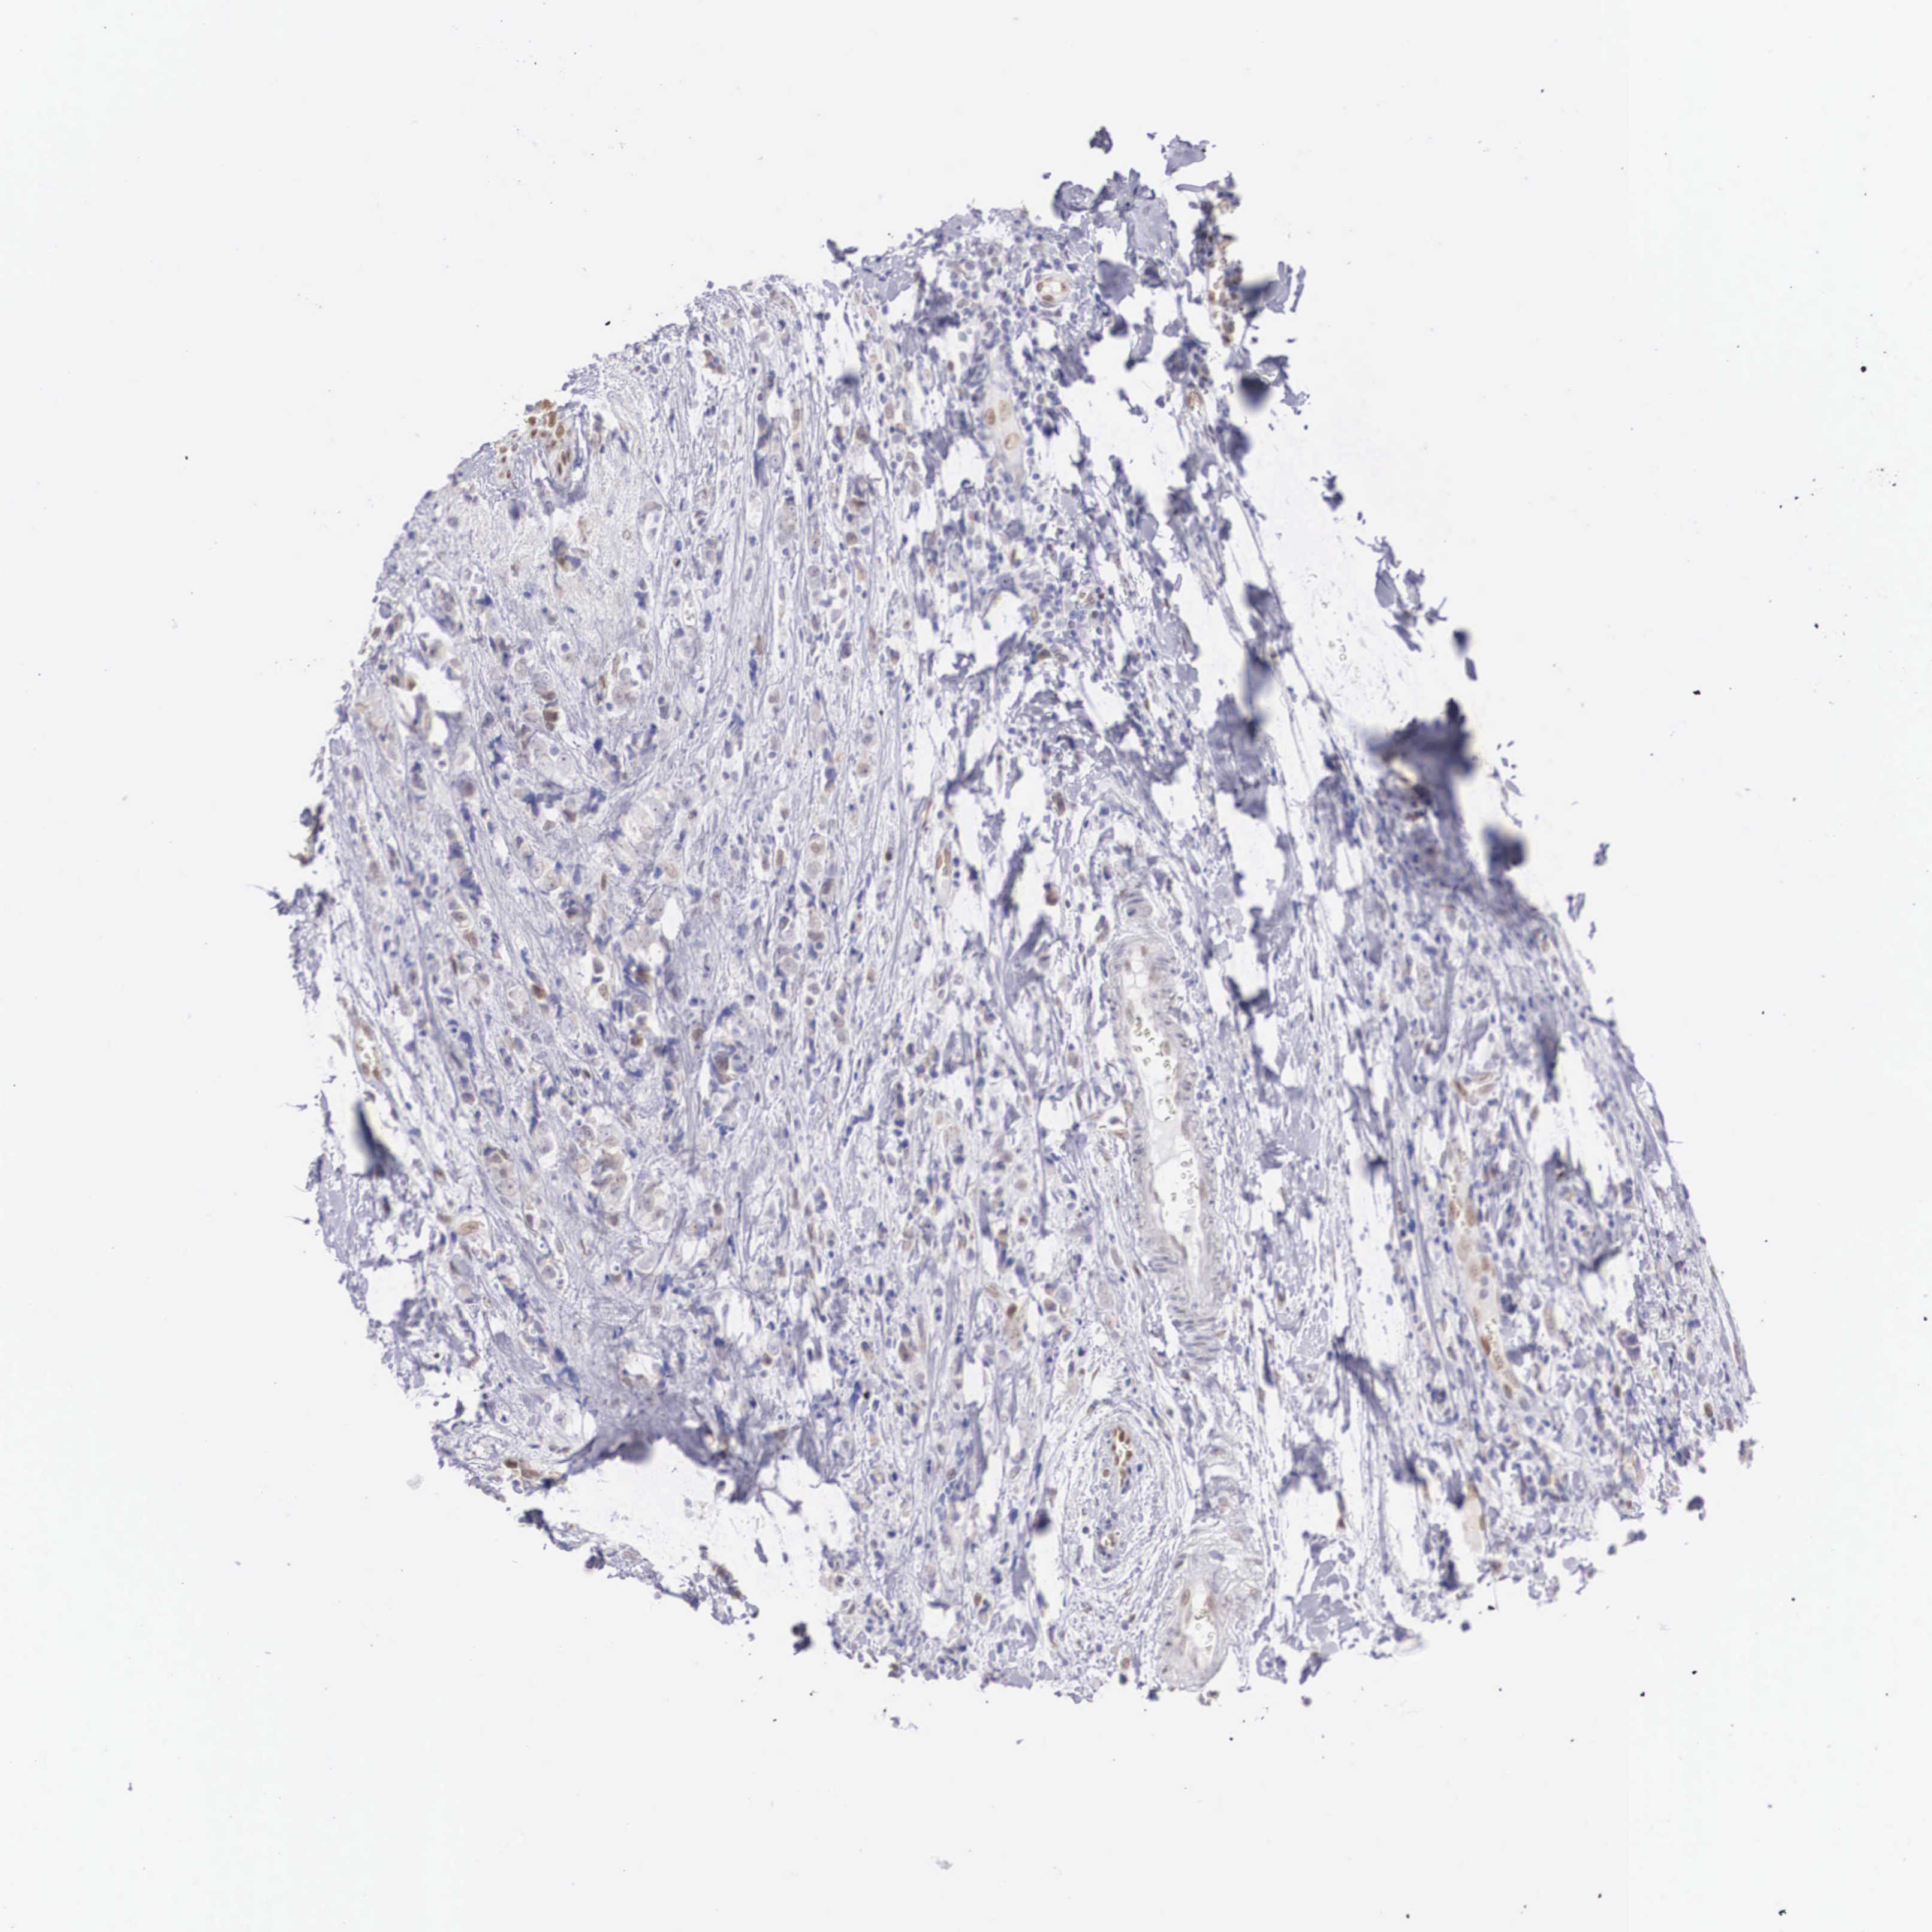

BRCA TCGA BRCA VALIDATION PROTEIN EXPRESSION

ANTIBODIES

AND

VALIDATION